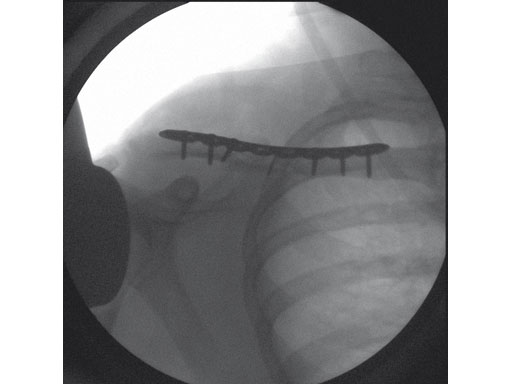

Fig 1ab Preoperative x-rays.